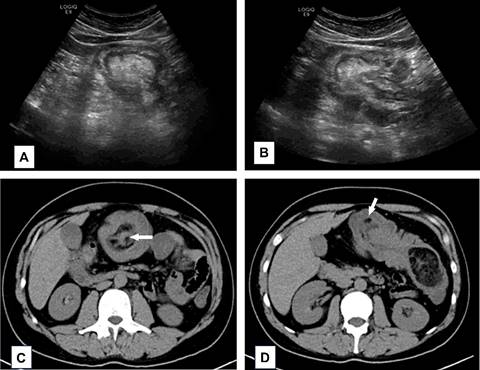

En prueba analítica se objetiva leucocitosis leve con desviación hacia la izquierda y elevación de proteína C reactiva. Se realiza ecografía abdominal, detectándose en mesogastrio lesión heterogénea “en blanco” con alternancia de capas hipo e hiperecoicas. Se completa estudio con tomografía computarizada que confirma invaginación colocólica de aproximadamente 19 cm de longitud, localizada en colon transverso con arrastre mesentérico y tumor de 5 cm de diámetro hipodenso con septos hiperdensos, con valores de atenuación en rango graso, sugestivos de lipoma. Se asocia trabeculación de la grasa del mesocolon transverso y distensión retrógrada del ciego y del colon ascendente (Figura 1).

Figura 1: A y B) Imágenes ecográficas en las que se objetiva colon transverso con imagen en “diana” correspondiente con intususcepción. C y D) Imágenes de tomografía computarizada en plano axial en las cuales se ve intususcepción intestinal alrededor de imagen hipodensa (flecha blanca) correspondiente con lipoma.